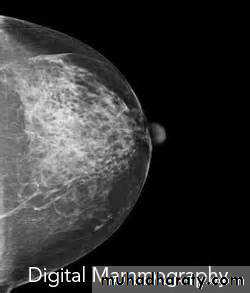

A digital mammography system tends to require a lower radiation dose than film screen mammography for the same image quality. Digital detector converts the X-ray photons to an electronic signal, which is further processed and displayed as a gray scale image. This image can either be electronically sent to a viewing station and displayed on a high-resolution monitor or printed and read on luminant-view boxes similar to how the film screen mammograms are read.

The digital system provides greater contrast resolution and thus better visualization of skin, peripheral breast tissue, and dense breasts. Besides this, it allows for changes in zoom, contrast, and brightness, which increase the ability to detect subtle abnormalities.

A film screen system does not offer such facilities and also tends to suffer from artifacts during processing and storage. These deficiencies are, however, partly compensated for by the advantage of a higher spatial resolution in film screens as compared to digital systems. However, despite of all these technological differences, studies have shown that the overall diagnostic accuracy was similar with these 2 modalities except for premenopausal and perimenopausal women in whom digital mammography was found to be more accurate. This is at least partly because digital mammography is relatively more sensitive than film mammography in detecting cancer in dense breasts.